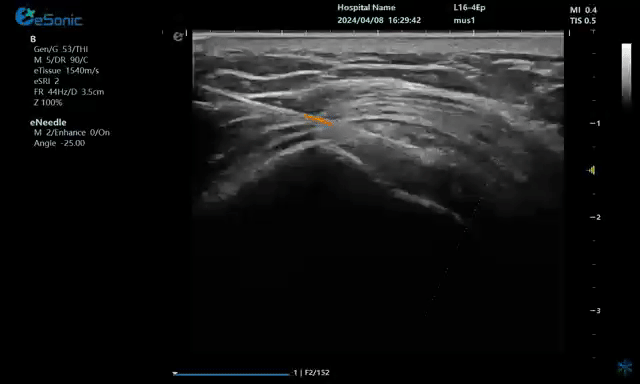

病例:冈上肌肌腱钙化穿刺治疗

640 (1).gif

注射药物

无磁导航技术引导穿刺钙化点